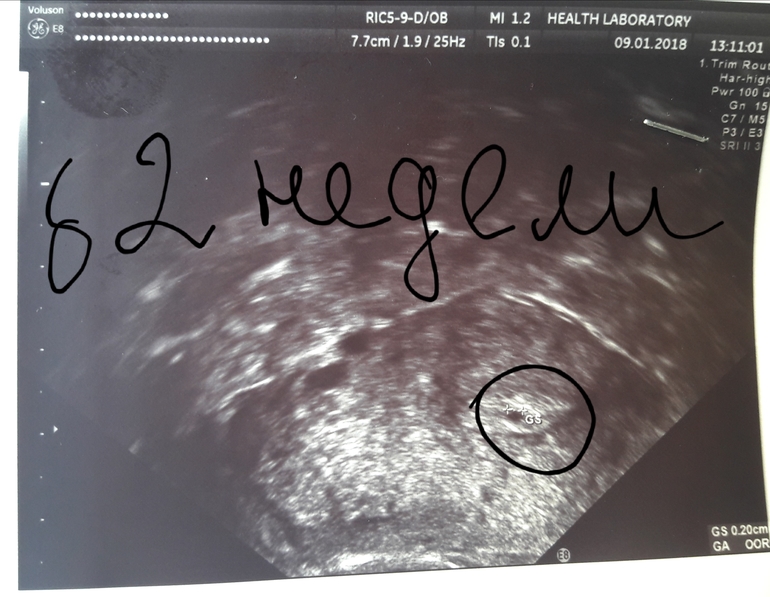

Была в 5 ак недель-плодное яичко 2 мм в матке,срок 2 недели.Повторное узи через 10 дней